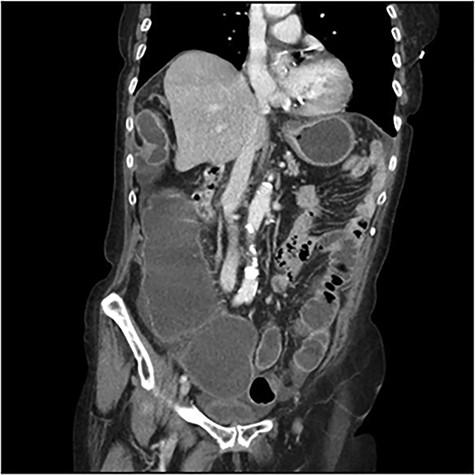

The scanner demonstrated a colonic occlusion resulting from an incarceration, which was diagnosed as a hernia of Bochdalek containing the hepatic angle of the colon (Fig. 2–4).

: CT scan images demonstrating a right diaphragmatic hernia containing intestine.

At the relecture of the images, they showed two old rib fractures. When asked to the patient, she mentioned a past history of a fall 2 years earlier, which directed us to the diagnostic of delayed right diaphragmatic rupture.

CT scan images demonstrating a right diaphragmatic hernia containing intestine.